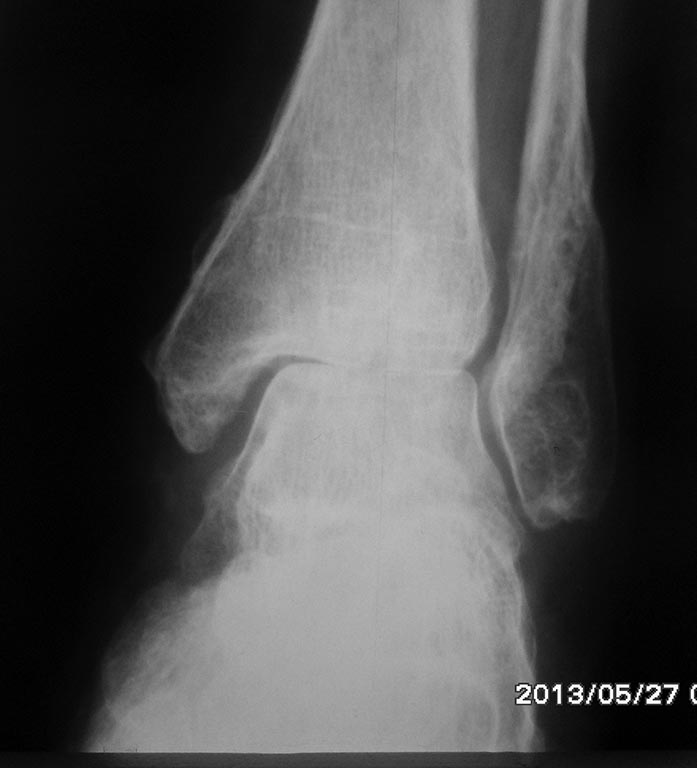

[Ortho] протезирование г/стопного сустава

здрвствуйте! вот снимки. наши пациеты протезируются в основном в

Астрахани и Саратове, редко в Москве.

Имя     : SAM_0950.JPG